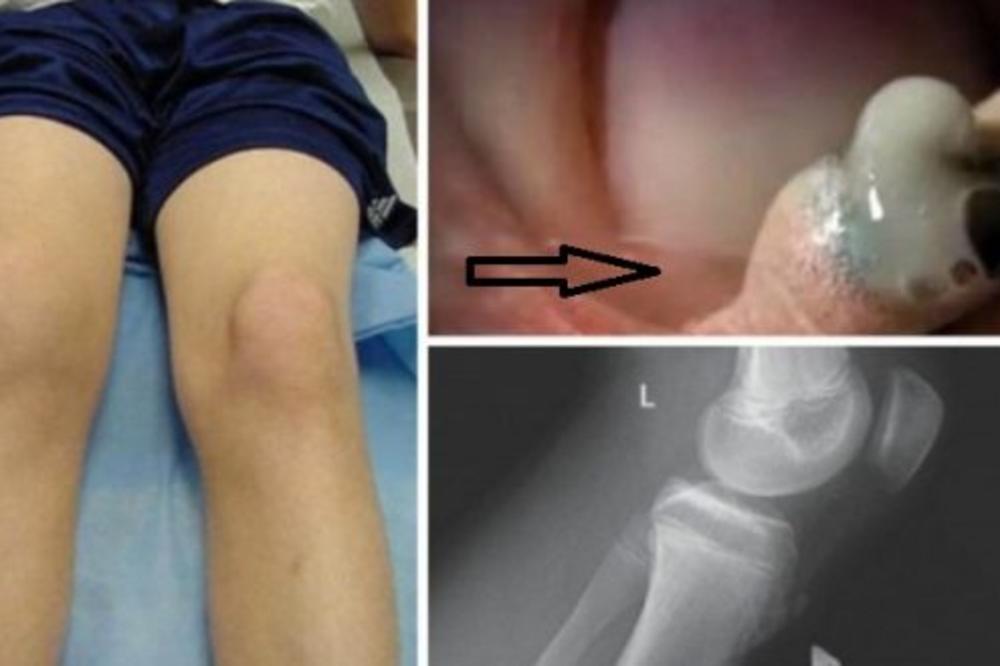

Niko nije mogao verovati da će ovo izaći iz manje rane na detetu, ali 4-godišnji Paul Franklin doživeo je upravo to. Jednog dana se kao i obično igrao na plaži, međutim pao je na stenu i tako povredio koleno.

Kada je rana nabubrila, njegova mama Rachael odvela ga je u hitnu. Lekar ih je obavestio da dete ima infekciju. Međutim, rana nije izlečena iako je nesrećni dečak dobio antibiotsku terapiju.

Rachael je primetila da je koleno počelo da crni. Tada je odlučila na svoju ruku da stisne ranu iako lekar nije preporučio takvu stvar.

Kada je to uradila, nešto šokantno se dogodilo, crni puž je izašao iz kolena! “Ovo se mrda!” Rachael je vrisnula. “Tu je puž unutra! Mehurići izlaze! ”

Ken, Paulov otac kaže da je sigurno njegov sin pao na puževo skrovište na toj steni. Tako je puževo jaje uspelo preko rane da završi u njegovom kolenu. Danas je Paulovo koleno potpuno zdravo te je čak dao ime pužu – Turbo!